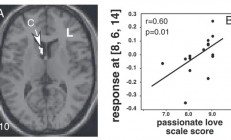

人为什么会“恋爱脑” 到底是不是病